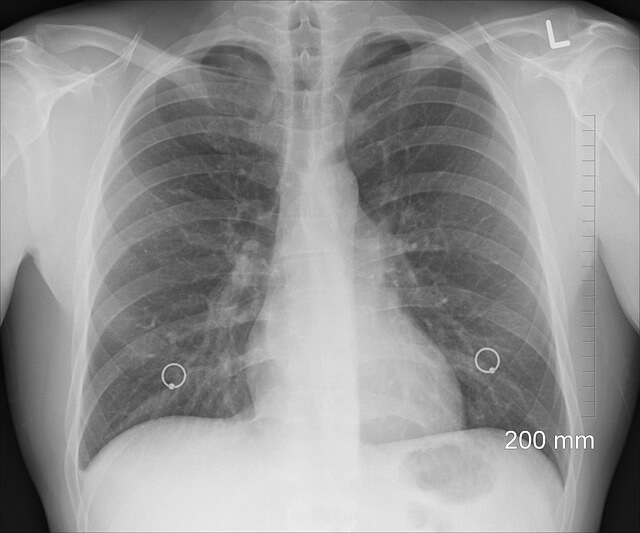

흉수 배액술이 필요한 경우

흉수(폐 주변에 물이 찬 상태)가 심하면 흉수 배액술이 필요할 수 있습니다.

치료 방법 설명 비고

흉수 배액술 흉부에 카테터를 삽입하여 물을 제거 심한 경우 필요

흉막 유착술 흉막 사이의 공간을 막아 재발 방지 재발 방지를 위해 사용